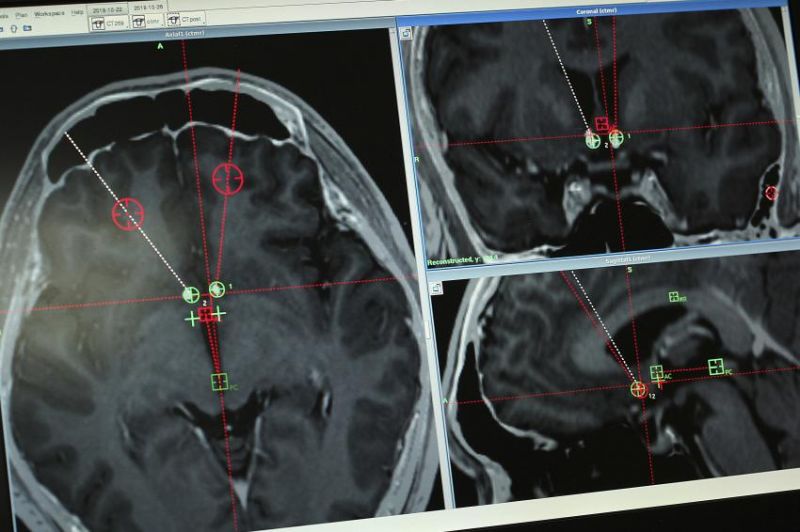

ਬੀਜਿੰਗ : ਚੀਨ ਦੇ ਵਿਗਿਆਨੀ ਨਸ਼ਿਆਂ ਦੀ ਆਦਤ ਛੁਡਾਉਣ ਲਈ ਪੇਸਮੇਕਰ ਟੈਸਟ ਦਾ ਇਲਤੇਮਾਲ ਕਰ ਰਹੇ ਹਨ। ਉਂਝ ਆਮ ਤੌਰ 'ਤੇ ਡਾਕਟਰ ਦਿਲ ਦੇ ਮਰੀਜ਼ਾਂ ਦੀ ਧੜਕਣ ਬਰਾਬਰ ਕਰਨ ਲਈ ਇਸ ਦਾ ਇਸਤੇਮਾਲ ਕਰਦੇ ਹਨ। ਇਸ ਲਈ ਪਹਿਲੀ ਵਾਰ ਚੀਨ ‘ਚ ਟੈਸਟ ਸ਼ੁਰੂ ਕੀਤੇ ਗਏ ਹਨ। ਡੀਪ ਬ੍ਰੇਨ ਸਟਿਮੂਲੇਸ਼ਨ (ਡੀਬੀਐਸ) ਤਕਨੀਕ ਜ਼ਰੀਏ ਵਿਗਿਆਨੀ ਸਿਰਫ ਇੱਕ ਬਟਨ ਦਬਾ ਕੇ ਹੀ ਲੋਕਾਂ ਵਿੱਚੋਂ ਨਸ਼ੇ ਦੀ ਆਦਤ ਖ਼ਤਮ ਕਰਨਾ ਚਾਹੁੰਦੇ ਹਨ।

ਇਸ ਤੋਂ ਪਹਿਲਾਂ ਪਾਰਕਿਨਸਨ ਵਰਗੀਆਂ ਬਿਮਾਰੀਆਂ ‘ਚ ਦਿਮਾਗ ਨੂੰ ਠੀਕ ਰੱਖਣ ਲਈ ਪੇਸਮੇਕਰ ਦਾ ਇਸਤੇਮਾਲ ਕੀਤਾ ਗਿਆ ਹੈ। ਇਸ ਤਹਿਤ ਮਰੀਜ਼ ਦੀ ਖੋਪੜੀ ਵਿੱਚ ਦੋ ਛੋਟੇ-ਛੋਟੇ ਛੇਕ ਕੀਤੇ ਜਾਂਦੇ ਹਨ ਤੇ ਪੇਸਮੇਕਰ ਨੂੰ ਦਿਮਾਗ ਨਾਲ ਜੋੜ ਕੇ ਬਿਜਲੀ ਜ਼ਰੀਏ ਉਤੇਜਨਾ ਪੈਦਾ ਕੀਤੀ ਜਾਂਦੀ ਹੈ। ਇਸ ਤਕਨੀਕ ਨੂੰ ਡੀਪ ਬ੍ਰੇਨ ਸਟਿਮੂਲੇਸ਼ਨ (ਡੀਬੀਐਸ) ਕਿਹਾ ਜਾਂਦਾ ਹੈ। ਕਿਸੇ ਮਰੀਜ਼ ਦਾ ਨਸ਼ਾ ਛੁਡਾਉਣ ਲਈ ਇਹ ਪਹਿਲਾ ਪ੍ਰਯੋਗ ਹੈ।